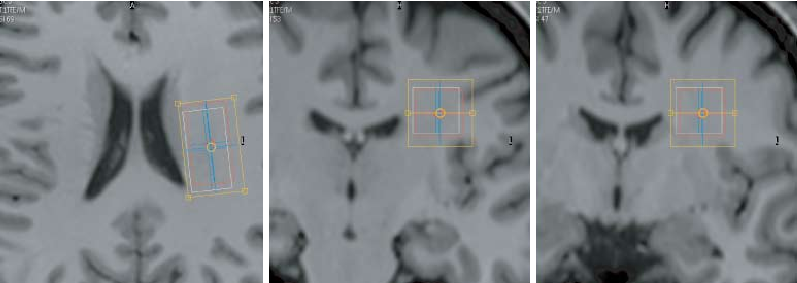

Figure 2

Reduced excitatory neurotransmitter levels in anterior insulae are associated with abdominal pain …